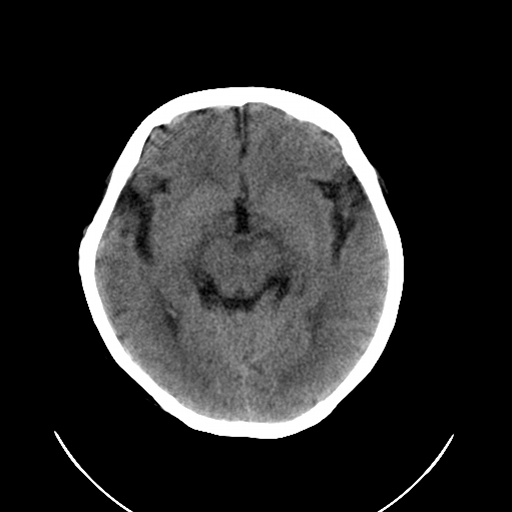

标题: CL0976:颅骨凹陷征 [打印本页]

标题: CL0976:颅骨凹陷征

女,56岁,头痛,没有其他的神经系统的阳性体征

颅底陷入是枕大孔周围骨,包括枕骨基底部、髁部和鳞部上升向颅腔内陷入的畸形。环、枢椎也随之上升、突入。多属枕骨及环枢椎先天性发育异常,也可继发于引起颅底软化的疾病、成骨不全或佝偻病等。

颅底凹陷症!这样横断位未见过,平时都是颈椎侧片所示。建议颈椎mr检查。

颅底凹陷是压迫小脑所以应该有受压的症状,如走路不稳,醉酒状态等.

颅底凹陷.典型.